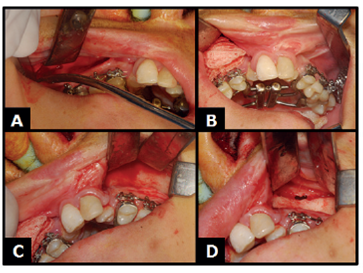

Em seguida, com o cinzel reto foi conferida a osteotomia desde o pilar zigomático, até as placas do pterigoideo -processos pterigoideos do osso esfenoide- em ambos os lados (Figuras 3A e 4A, 4B).

A) Cinzel reto para conferir a osteotomia; B) Disjunção pterigomaxilar.

Figura 4: A) Cinzel reto para conferir a osteotomia; B) Disjunção pterigomaxilar.

Fonte: Documento obtido durante o estudo.

Logo após, com auxílio da chave de ativação foi acionado o parafuso do aparelho expansor tipo Hyrax (Figuras 5A, 5B e 5C), instalado previamente à realização da cirurgia, no intuito de confirmação da ocorrência de separação passiva das osteotomias.

A) Hemostasia; B) Acionamento do aparelho expansor tipo Hyrax durante o ato cirúrgico; C) Ativação do aparelho.

Figura 5: A) Hemostasia; B) Acionamento do aparelho expansor tipo Hyrax durante o ato cirúrgico; C) Ativação do aparelho.